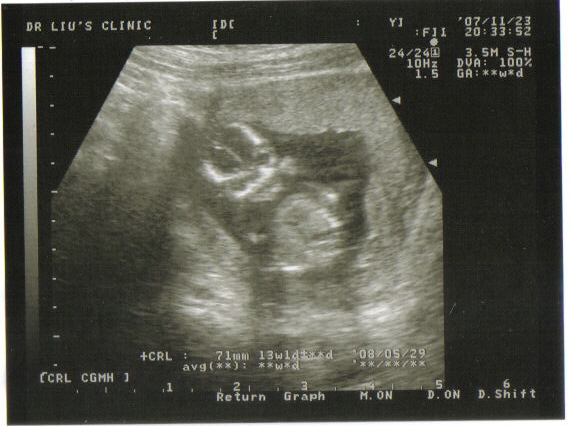

小米跟上次比較起來~

這次最不一樣的就是他的五官可以明顯的看出來了~

大家看的出來嗎~~~整個就像個外星寶寶一樣~~

小米跟上次比較起來~

這次最不一樣的就是他的五官可以明顯的看出來了~

大家看的出來嗎~~~整個就像個外星寶寶一樣~~